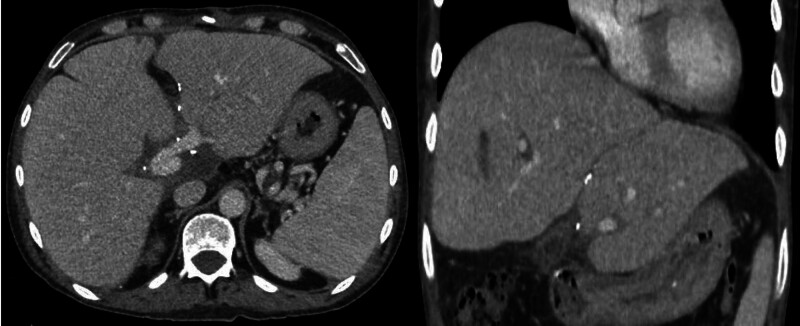

Brief report: A 2-y-old child with Maple syrup urine disease and a 40-y-old adult with end-stage liver disease became the focus of this unique case. A hybrid dual graft liver transplant was executed, uniting the domino donor's full organ graft with a living donor's left lateral segment. Precise vascular and biliary reconstructions facilitated a successful transplant.

Abstract Image